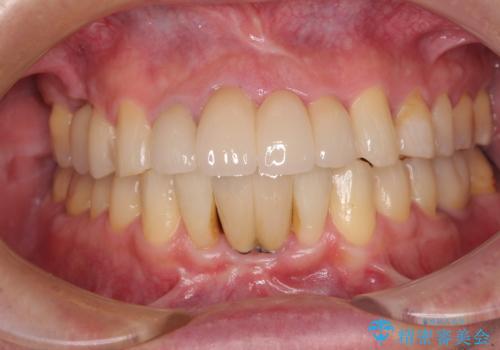

重度のがたつき 矯正治療+セラミック治療で綺麗な歯並びに 矯正専門では難しい治療

担当医 井上季実子